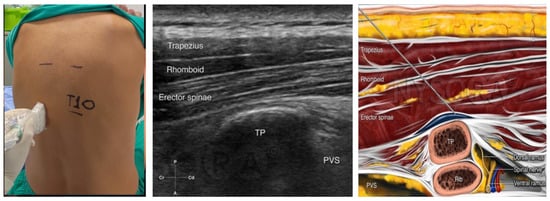

Bilateral erector spinae plane block (ESPB) was administered to all participants while in the seated position, 30 min before the initiation of general anesthesia. This procedure was performed under ultrasound guidance, utilizing a linear transducer (7–13 MHz) and an 80 mm, 22-gauge, short bevel needle. Initially the transducer was placed transversely on the spinous process of T10, and 3 cm laterally, the transverse process of T10 was identified. Subsequently, the transducer was repositioned sagittally, and the correct landmarks were identified. The needle was then inserted in a cephalad-to-caudad orientation, employing an in-plane technique. The needle was advanced, and 20 mL of the prepared solution was administered in the fascia between the transverse process and the erector spinae muscle, at each side. After completion of the block, a catheter for the continuous infusion of local anesthetic was inserted on each side (see Figure 1).

Figure 1. Erector spinae plane block. The transducer is placed in transverse position on the preferred spinous process, and 3 cm laterally, the transverse process of the vertebra that is selected is identified. The transducer is turned sagittally, and the landmarks (trapezius muscle, rhomboid muscle, erector spinae muscle, and transverse process) are identified. The needle is inserted in a cephalad-to-caudad orientation and an in–plane technique is performed. The needle is advanced until its tip reaches the fascia between the transverse process and the erector spinae muscle and the local anesthetic is administered [8]. The figure was reprinted with permission from source: NYSORA.COM.